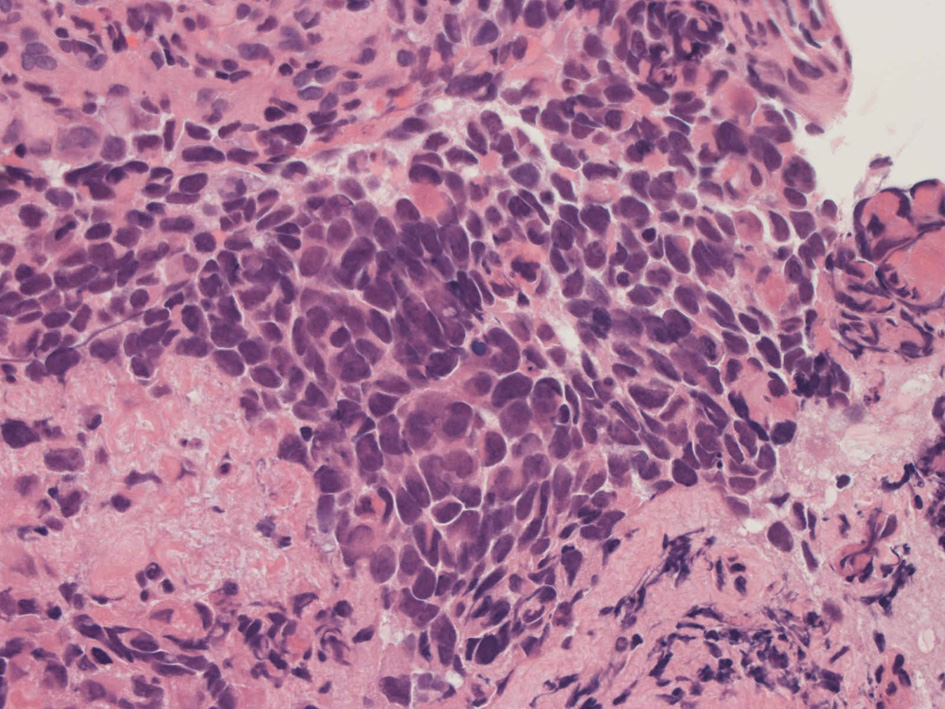

Alveolar rhabdomyosarcoma

Alveolar rhabdomyosaroma

Undifferentiated small round cell tumors of the sinonasal tract

rhabdomyosarcoma 横紋筋肉腫

40歳女性 鼻粘膜腫瘤

右頸部のしこりを自覚。近医MRIで頸部多発リンパ節腫大あり当院を紹介される。右顎下, 右鎖骨上窩にも多数のリンパ節を触れる。穿刺細胞診ではcarcinoma疑い。右鼻腔, 上顎洞にも腫瘤が認められリンパ節腫大との関係を調べるために鼻腔腫瘤の生検が行われる。

病理組織所見